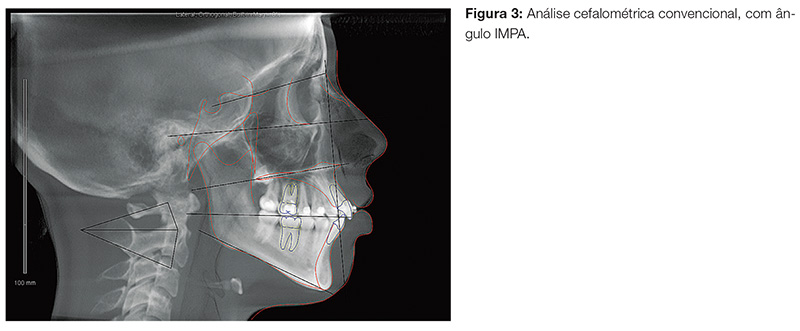

Em nosso prática clínica, dados obtidos rotineiramente em análises cefalométricas 2D são confirmados em detalhes e personalizados por regiões com o uso de imagens 3D obtidas a partir de tomografias do tipo cone beam. A inclinação de incisivos superiores e inferiores é um exemplo típico. Normalmente medidos por ângulos como o IMPA, o uso de imagens 3D e de softwares de visualização dessas imagens nos permite personalizar a inclinação dos dentes em relação à sua base óssea, e não a uma sobreposição de imagens.

Na Figura 3, nota-se o ângulo dos incisivos inferiores medido em uma cefalometria convencional. Ao realizarmos cortes 3D a partir de uma tomografia, pode-se identificar com maior facilidade o grau de discrepância e inclinação de cada dente em relação à sua base alveolar (Fig. 4). Um maior grau de precisão em termos de direcionamento e movimentação dos dentes em questão pode ser planejado e obtido com a mecânica correta.